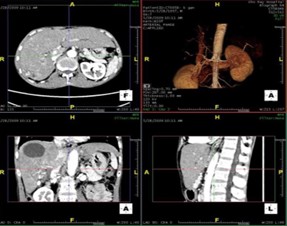

Những năm vừa qua được sự quan tâm của thủ trưởng các cấp cùng với sự đầu tư của Đảng ủy, Ban giám đốc Bệnh viện trong chẩn đoán và điều trị, bệnh viện đã trang bị nhiều máy móc hiện đại, trong đó đặc biệt có máy CT Scanner 16 Slice SIEMENS của Cộng Hòa Liên Bang Đức, cùng với sự chuyển giao kỹ thuật, công nghệ mới, các bác sỹ và kỹ thuật viên đã làm chủ hoàn toàn các kỹ thuật phức tạp mà chỉ có tuyến tỉnh và trung ương mới đáp ứng được như: Chụp CTscanner có thuốc cản quang gan ba thì, ổ bụng, lồng ngực, sọ não, hệ mạch máu bụng, chậu, chi…Trong thu dung cấp cứu, máy CT Scanner càng phát huy thế mạnh trong chẩn đoán chấn thương sọ não, chấn thương bụng kín…